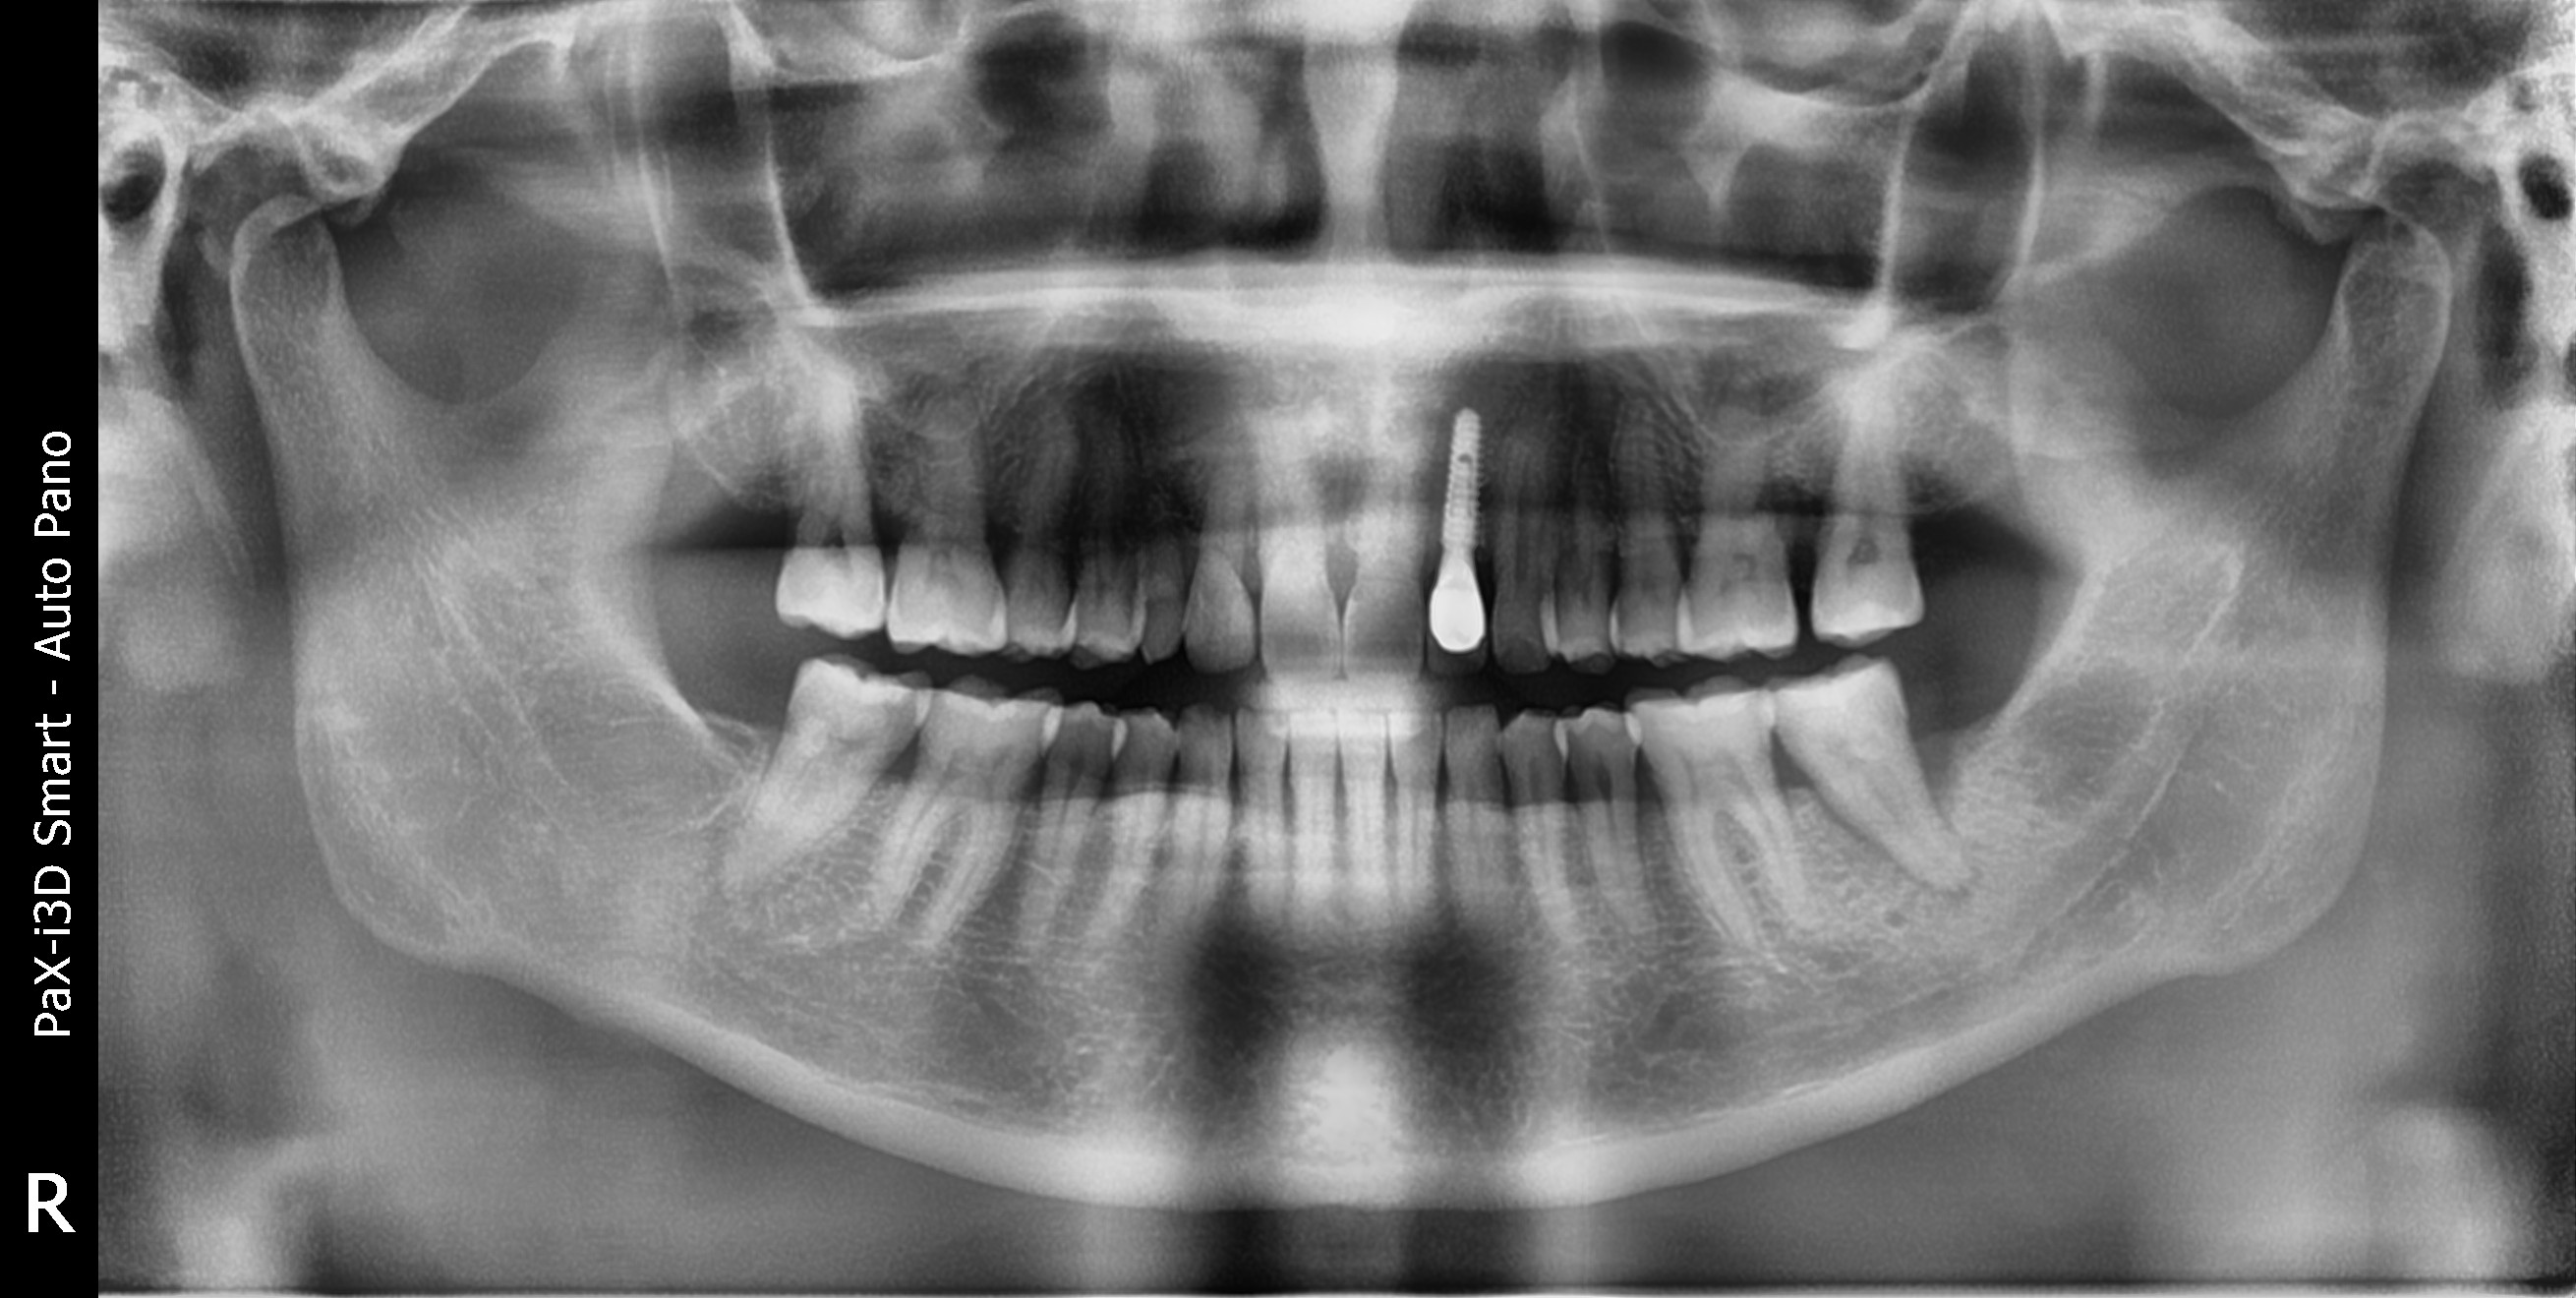

Before

발치후 즉시 임플란트